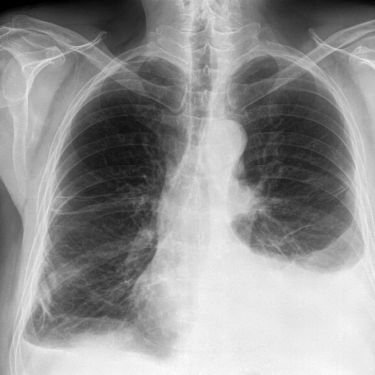

Advanced Diagnostic & Treatment Facilities